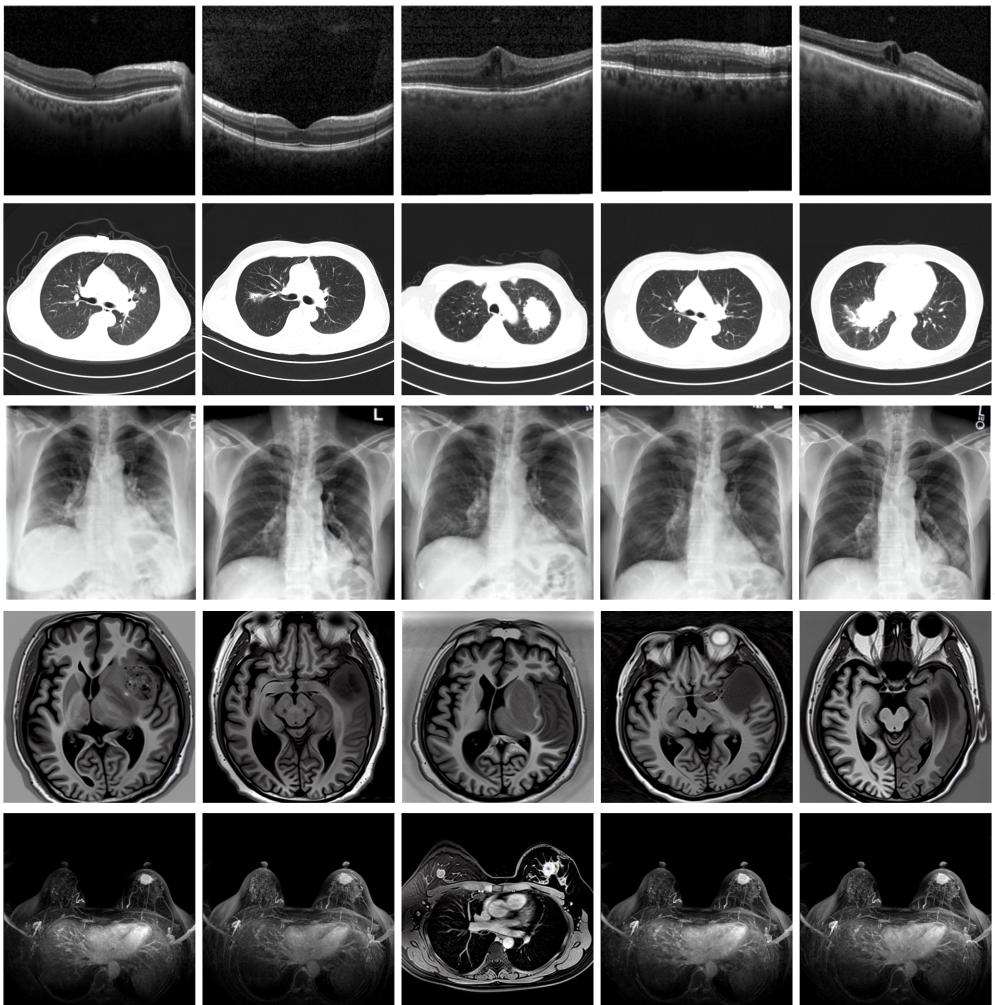

圖為由MINIM生成的高質(zhì)量醫(yī)學合成圖像(受訪者供圖)

“目前公開的醫(yī)學影像數(shù)據(jù)非常有限,我們建立的生成式模型有望解決訓練數(shù)據(jù)不夠的問題?!北本┐髮W未來技術(shù)學院助理研究員王勁卓說,研究團隊利用多種器官在CT、X光、磁共振等不同成像方式下的高質(zhì)量影像文本配對數(shù)據(jù)進行訓練,最終生成海量的醫(yī)學合成影像,其在圖像特征、細節(jié)呈現(xiàn)等多方面都與真實醫(yī)學圖像高度一致。

實驗結(jié)果顯示,MINIM生成的合成數(shù)據(jù)在醫(yī)生主觀評測指標和多項客觀檢驗標準方面達國際領(lǐng)先水平,在臨床應用中具有重要參考價值。在真實數(shù)據(jù)基礎上,使用20倍合成數(shù)據(jù)在眼科、胸科、腦科和乳腺科的多個醫(yī)學任務準確率平均可提升12%至17%。